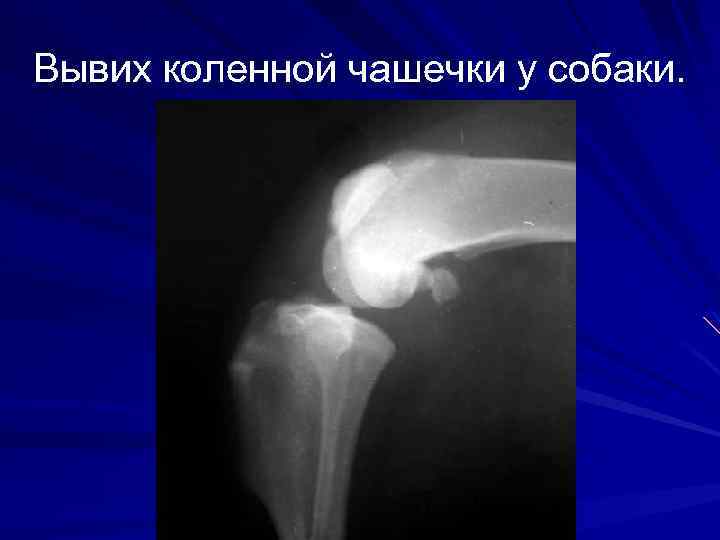

Вывих коленной чашечки у собаки.

2. Закрытые травматические асептические болезни суставов. 1. Ушиб сустава. 2. Растяжение сустава- кратковременное чрезмерное смещение костей с частичными разрывами капсулы сустава и его связок. 3. Вывих и подвывих сустава- повреждение сустава, сопровождающееся стойким смещением костей, разрывами капсулы сустава и связок, сопровождаются гемартрозом. Бывают патологические, травматические и врожденные. 4. Параартикулярный фиброзит- образование в параартикулярных тканях большого количества фиброзной ткани. 5. Контрактура сустава.